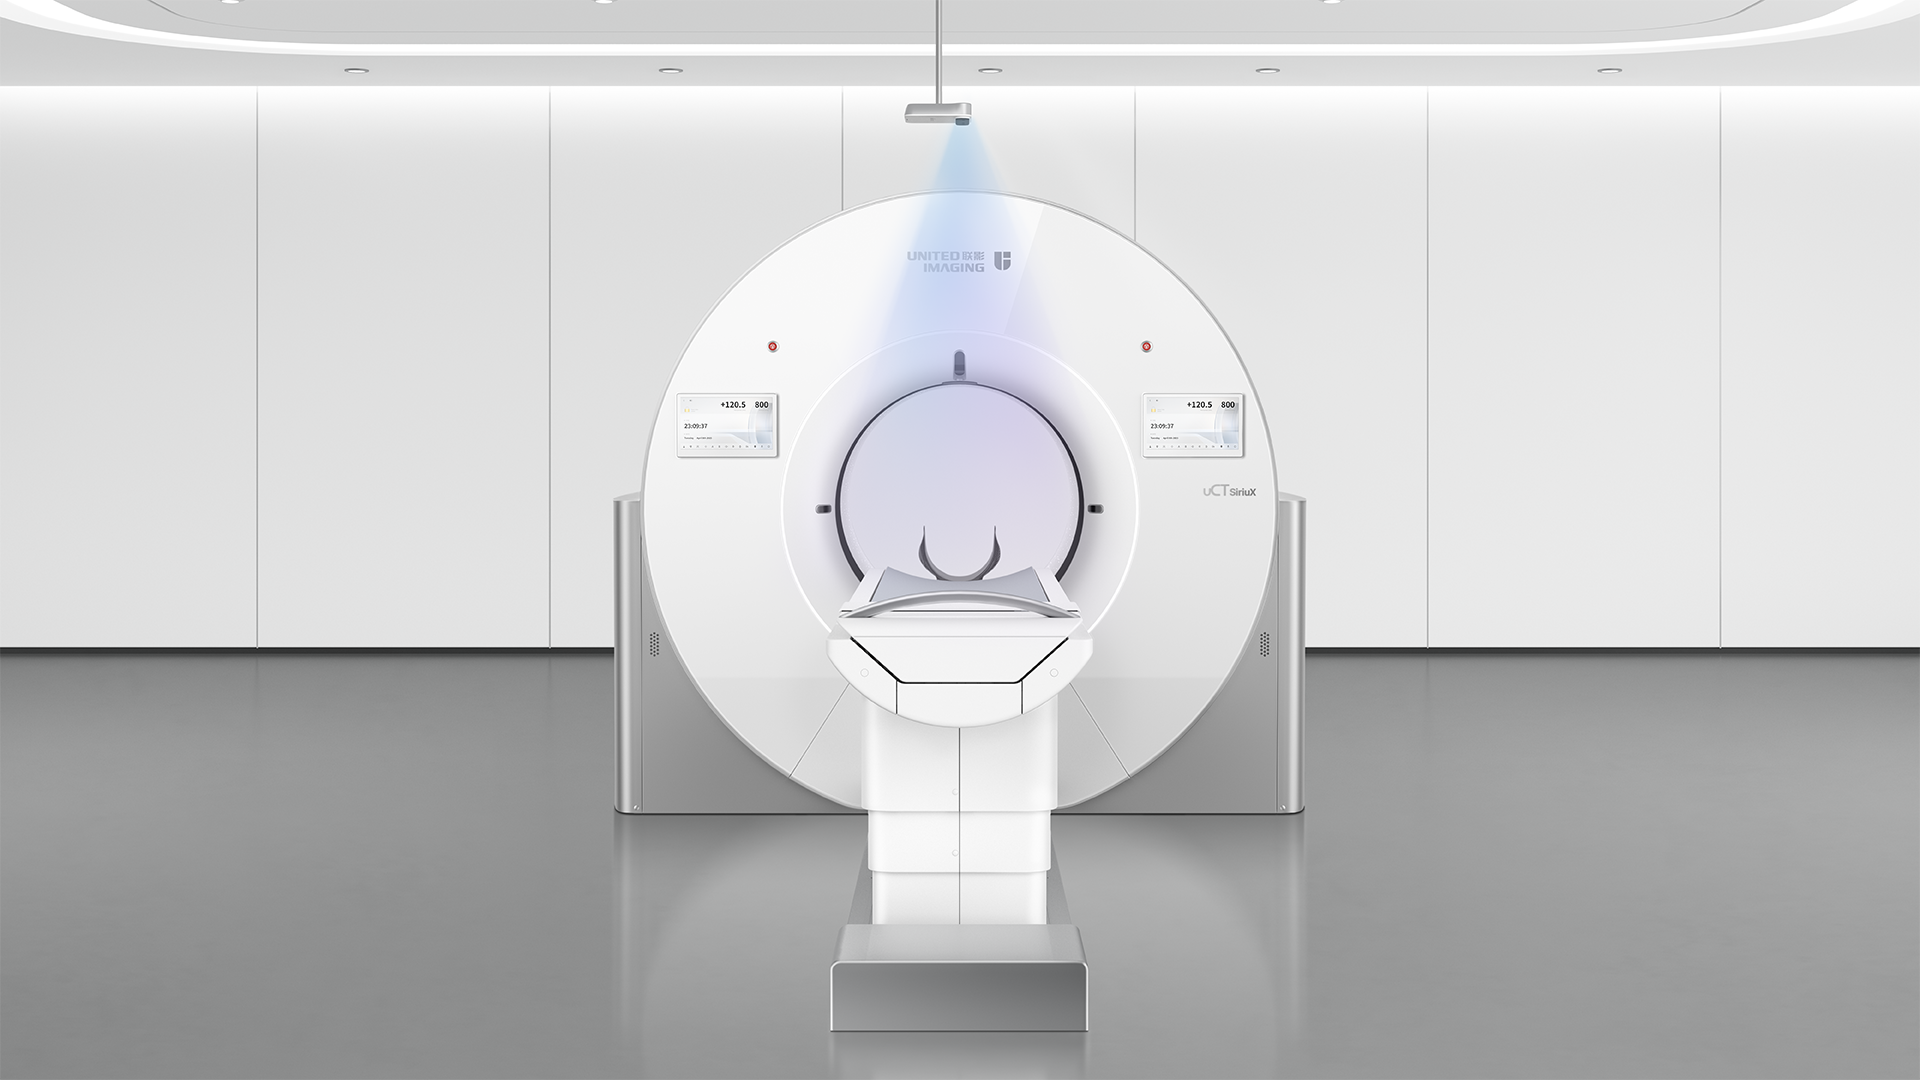

超越旗舰 · 更上心境

CT技术正经历一场从“静态看清解剖”到“动态看懂功能”的深刻变革。双宽体双源CT系统 uCT SiriuX®,首度融合宽体探测器与双源架构,在时间、覆盖与精准度上实现全面飞跃。从心脏搏动到全身脏器,从细微解剖到动态变化,皆清晰可见。技术之上,更为看见生命每一次律动。